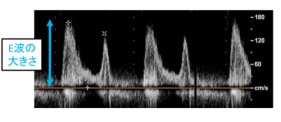

2018/12/14  国立循環器病研究センター国立循環器病研究センター(略称:国循)心不全科の岡本千聡医師、岡田厚医師、泉知里部長らの研究チームは、無症状で心機能の保たれた僧帽弁逆流症(器質性)患者における、心エコー図検査を用いた新たな予...